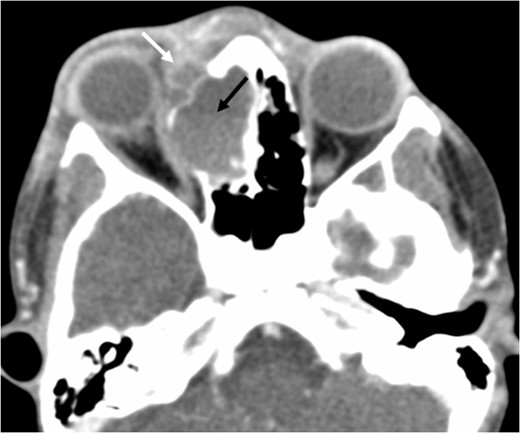

Axial T1 post-contrast sequence with fat suppression demonstrating peripheral enhancement (white arrows) but no internal or solid enhancing components to suggest that this is a secondary ABC.

At this point the MRI was reviewed and the possibility of an ABC was raised. This was due to the presence of fluid–fluid levels, cyst within a cyst appearance and lack of restricted diffusion within the sinonasal contents and material drained at the time of the first endoscopic procedure. He was discharged home on oral co-amoxiclav, and topical betamethasone nose drops.